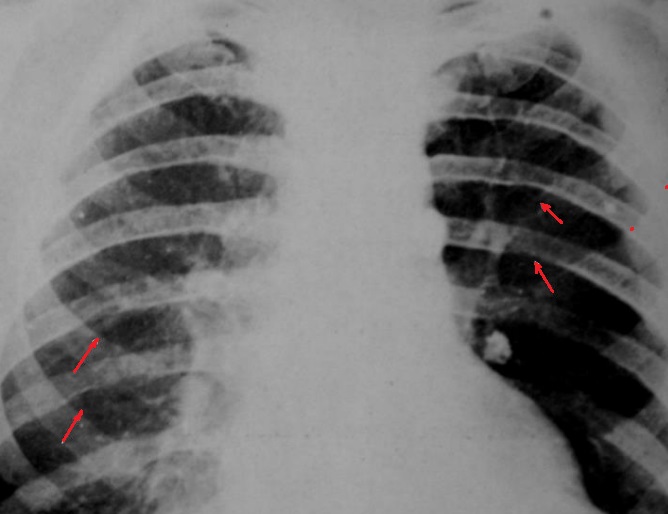

Image

radiologique standard PA pulmonaire de lyse costale

droit d'une lesion metastase costale |

Schéma du syndrome pariétal avec lésion osseuse. 1.

opacité en regard d'une ostéolyse costale ; 2. floue

en haut,

bien limitée en bas; 3 raccord

en pente douce |